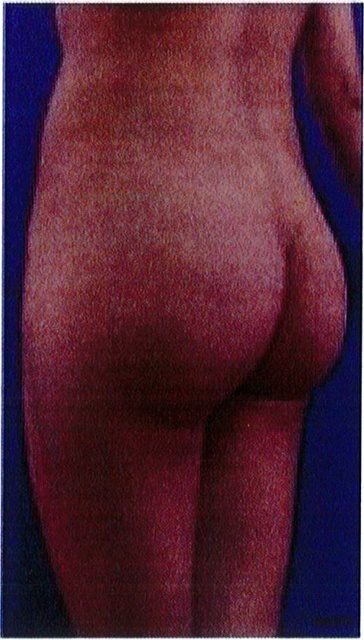

Hình. 18.. (A) Hình anh trước và (B) và sau phẫu thuật làm đầy mông của bệnh nhân được đặt khối implant dưới cân thể tích 225 mL, hai bên.

Bệnh nhân 31 tuổi tiền sử khỏe mạnh, có chỉ định nâng mông bằng implant do thiếu hụt thể tích. Hai khối anatomic implant 225 mL polyurethane dạng gel được đặt ở vị trí dưới cân. Sau phẫu thuật không ghi nhận biến chứng trong suốt quá trình hồi phục, vết mổ liền tốt (Hình 18).